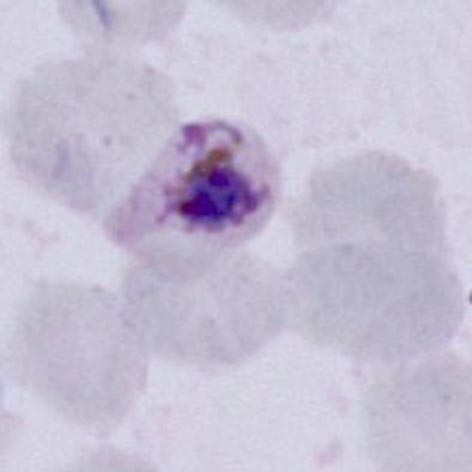

Gametocytes (like schizonts) are the final mature form of parasites in the blood, consequently they have metabolised all haemoglobin in order to grow. The red cell is therefore now simply a membrane that surrounds the parasite without any red colour, and with prominent malaria pigment that represents the metabolised haem iron. The appearance of gametocytes however does vary according to species and this can aid morphological species identification

P.malariae Like other stages in this species the red cell containing the parasite is not enlarged or distorted and may be small. Parasites are typically small and neat with rounded form that do not fill the red cell.